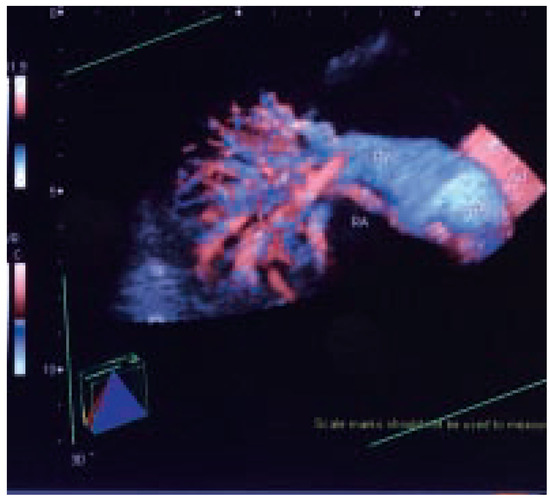

Dreidimensionale Angiosonographie

by Michel Zuber

Viele Gefässsysteme lassen... Full article

Show Figures

Figure 1